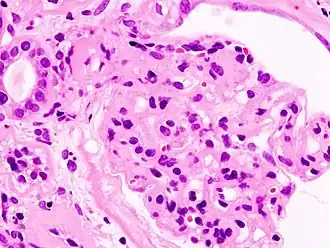

L'ultrafiltration du sang qui va donner l'urine primitive se fait dans le glomérule. Par un mécanisme physique (pression hydrostatique, pression oncotique) et biologique (sélectivité de la membrane glomérulaire aux composants sanguins), le plasma est filtré à travers la membrane basale glomérulaire (MBG) et les prolongements podocytaires qui la tapissent pour former l'urine primitive, laquelle sera ensuite successivement modifiée par les différentes structures rénales pour donner l'urine définitive. Le syndrome néphrotique est dû à une anomalie anatomique ou fonctionnelle de la membrane basale glomérulaire, qui est normalement imperméable aux protéines au-dessus d'un poids moléculaire de 60 kDa (60 000 daltons). La perte de cette sélectivité entraîne le passage de protéines dans les urines (qui apparaît lorsque les capacités physiologiques de réabsorption tubulaire des protéines sont dépassées), et donc la protéinurie et l'hypoprotidémie (malgré une synthèse accrue de protéines par le foie).

Un examen simple permet de différencier ces deux tableaux : l'évaluation de la sélectivité de la protéinurie. Une protéinurie composée à plus de 85 % d'albumine (principale protéine plasmatique) est dite sélective, et relève des anomalies fonctionnelles le plus souvent. Au contraire, une protéinurie non sélective témoigne le plus souvent d'anomalies anatomiques sévères ne touchant pas que la membrane basale glomérulaire.

- Amylose : par dépôt de protéines amyloïdes anormales dans les glomérules.

- Syndrome néphrotique idiopathique de l'enfant (ou de l'adulte) : par perte des charges négatives de la membrane basale glomérulaire qui normalement repoussent les protéines, elles aussi chargées négativement. (D'après les études épidémiologiques récentes[réf. nécessaire], il y aurait autant d'enfants que d'adultes atteint d'un syndrome néphrotique idiopathique).

- Néphropathie diabétique : par altération des capillaires liée à l'hyperglycémie chronique (trop de sucre dans le sang entraîne la glycation de nombreuses protéines, dont certaines fragilisent les parois des capillaires sanguins, en particulier des reins et de la rétine).

- Glomérulonéphrite extramembraneuse : par dépôt d'immunoglobulines G et de fractions du complément sérique à la face externe de la membrane basale glomérulaire.